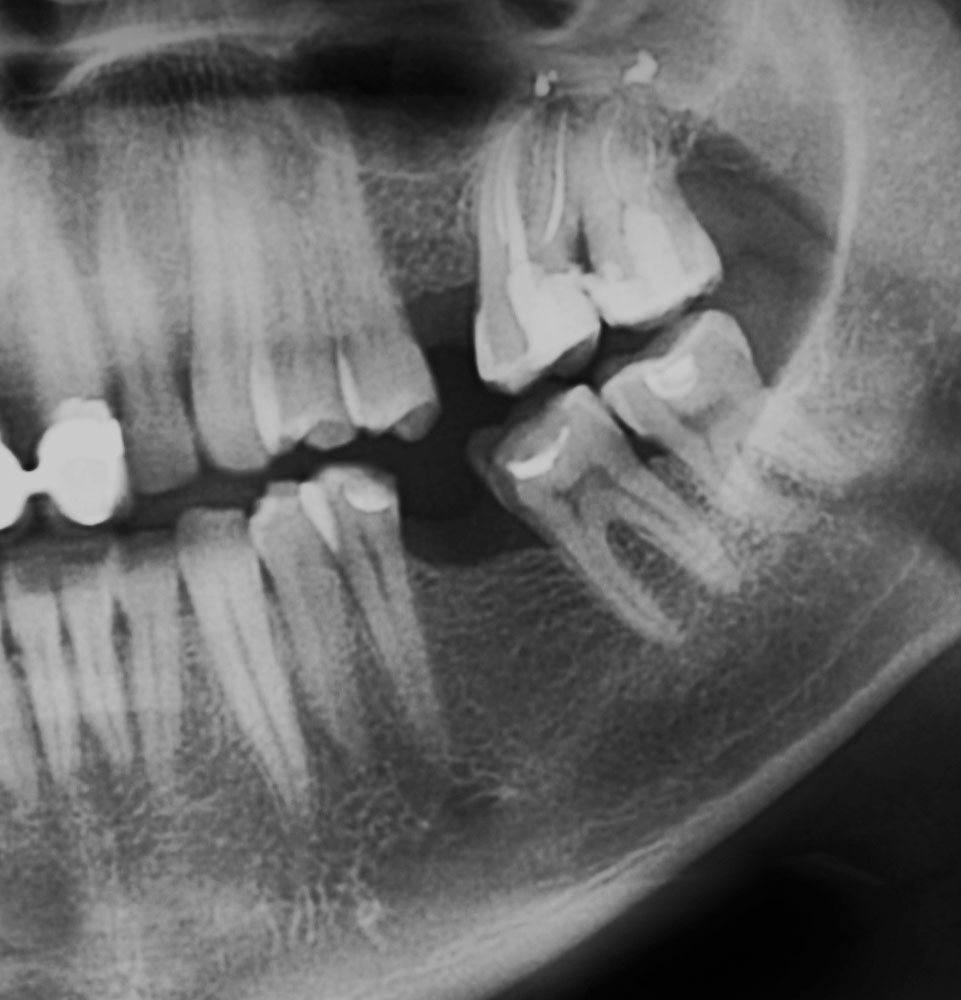

Before

After